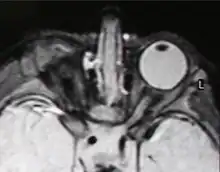

Right-sided anophthalmia (MR image)

MRIs and CTs can be used to scan the brain and orbits. Radiologists use this to assess the internal structures of the globe, the optic nerve and extraocular muscles, and brain anatomy.